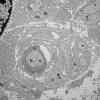

3A4 Case 3 EM